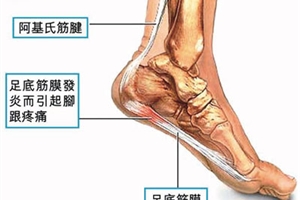

跟腱炎一般是由慢性、反复的跟腱劳损,或是有外伤诱发引起的,也有不少是骨质增生、骨刺等诱发引起的。跟腱炎属于软组织病变,尽管想要完全防止跟腱炎的发生是不可能的,但是可以采取一些措施来降低它的风险。